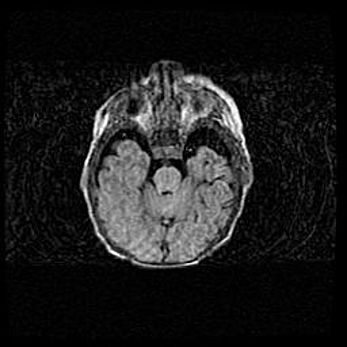

Лейкомаляция с кистозно-глиозной дегенерацией головного мозга.

Возраст: 2 месяца 25 дней

Вес: 6400 г

Окружность головы: 40 см

Срок гестации: 41 неделя

Лейкомаляцию относят к ишемически-гипоксическим повреждениям головного мозга, диагностируемым у новорожденных. При лейкомаляции в головном мозге обнаруживают очаги некроза, возникшие после тяжелой гипоксии и нарушения кровотока. В процессе морфогенеза очаги проходят три стадии: 1) развития некроза, 2) резорбции и 3) формирования глиозного рубца или кисты. Перивентрикулярная лейкомаляция (ПЛ) встречается примерно в 12% случаев среди новорожденных, обычно – у недоношенных детей, причем, частота ее зависит от массы, с которой младенец появился на свет. Наибольшее число малышей страдает лейкомаляцией, если масса при рождении 1500-2500 г.